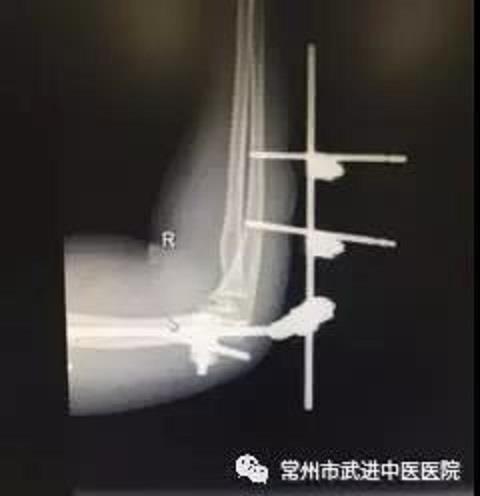

今年1月,王女士骑电动车不慎摔倒,导致右侧肘关节损伤,医院诊断为:肘关节脱位,冠状突骨折,桡骨小头骨折。王女士在全麻下行肘关节稳定术,术后予消肿、止痛等对症治疗处理。3个月后拆除外固定。

术后DR片(上)